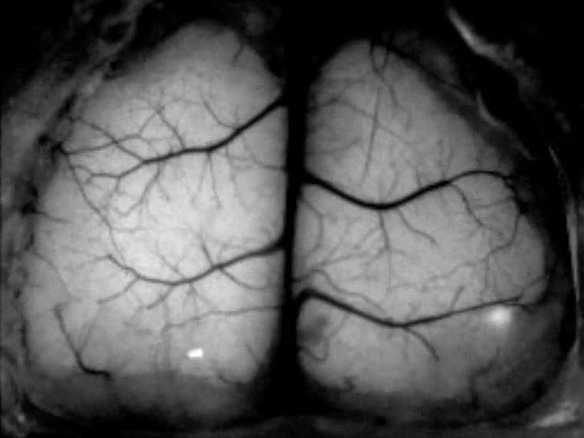

Сотрудники Университета Миннесоты разработали уникальный трехмерный имплантат для черепа. Примечателен он тем, что изготовлен из абсолютно прозрачного материала и позволяет следить за активностью поверхности мозга в режиме реального времени, пишет Medical Express. Пока имплантат опробовали только на мозге грызунов, но в перспективе он позволит пролить свет на неврологические недуги вроде болезней Альцгеймера и Паркинсона.

Для изготовления имплантата, полностью повторяющего по форме череп, ученым пришлось просканировать поверхность черепа грызуна. В отличие от ранее создававшихся имплантатов, которые давали лишь небольшое "окно", новый позволяет видеть большую часть коры головного мозга в действии, когда проводится искусственная стимуляция отдельных зон.

К примеру, ученые проверили, как умеренное сотрясение одной части мозга влияет на другие зоны по мере структурной и функциональной реорганизации неврологической системы. По словам разработчиков, имплантат не отторгался телом грызунов. Поэтому специалисты могли проводить исследование в течение многих месяцев, в том числе, занимаясь изучением процесса старения мозга.